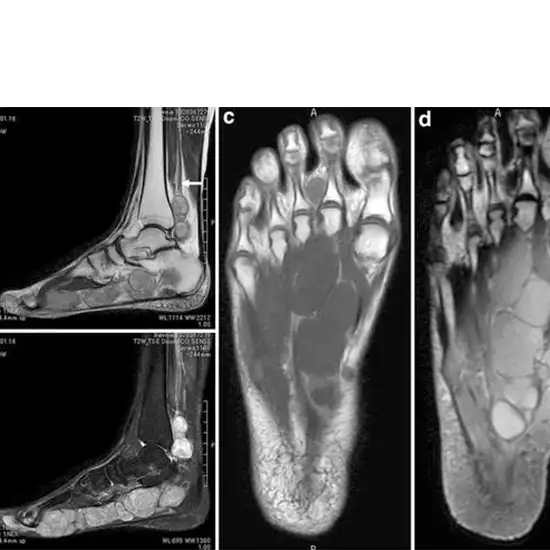

An MRI of the right foot with contrast reveals the bones and the soft tissues around them, such as tendons, ligaments, muscles, and blood vessels. The contrast improves the MRI's sensitivity and diagnostic accuracy by making internal organs more apparent.

This test is used to diagnose broken or fractured foot bones, osteoporosis, malformations, abnormal bone development, and arthritis (inflammation of the joints).